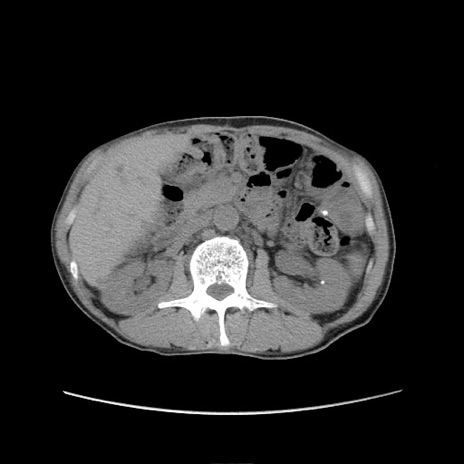

症例11(横断像)

【症例】 60歳代男性

【主訴】 下腹部痛

【現病歴】 本日夜中より下腹部痛の症状認め、受診。

【既往歴】 膀胱癌(膀胱全摘+尿管皮膚瘻術) 、胃癌術後

【身体所見】 BT 35.3℃、PR 58/min、BP 136/98mHg、腹部平坦、軟、腸蠕動音±、ストマ留置あり、左上腹部~正中部に圧痛あり、反跳痛なし。

【データ】WBC 5100、CRP0.01